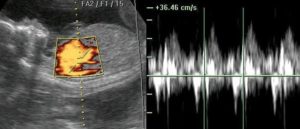

Это метод УЗИ, изучающий особенности кровотока и строения сердца. Частота сердцебиения плода отражает способность его организма справляться с дефицитом кислорода. Если он не врач, то вряд ли получится расслышать сердце раньше 25 недели беременности. Если беременность многоплодная, то сердце каждого ребенка слышно в разных отделах живота.

II и III триместр При проведении УЗИ на этих сроках беременности врач оценивает не только количество сердечных сокращений, но и их частоту, и расположение сердца в грудной клетке будущего ребенка.